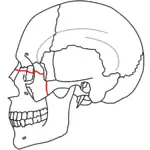

A principios del siglo XX, René Le Fort trazó ubicaciones típicas para las fracturas faciales, éstas ahora son conocidas como I, II y III fracturas de Le Fort (derecha).[5][2][6]

La fractura de Le Fort tipo I, también llamada Guérin o fractura del maxilar horizontal,[7][8] implican al maxilar superior, separándolo del paladar.[9]

La fractura de Le Fort tipo II, también llamada fractura piramidal del maxilar,[7][10] cruza los huesos nasales y el reborde orbitario.[9]

La Fractura de Le Fort#Lefort III, también llamada disyunción craneofacial y fractura facial transversal,[7][11] cruza la parte delantera del maxilar superior e implica al hueso lacrimal, a la lámina papirácea, y a la cavidad orbitaria, y a menudo implica al hueso etmoides,[9] es la más grave.[12] Las fracturas de Le Fort, que representan del 10% al 20% de las fracturas faciales, a menudo son asociadas con otras lesiones graves.[9]

Le Fort hizo sus clasificaciones basadas en el trabajo con cráneos de cadáveres, y el sistema de clasificación ha sido criticado por impreciso y simplista ya que la mayoría de las fracturas del tercio medio facial implican una combinación de las fracturas Le Fort.[9] A pesar de que la mayor parte de las fracturas faciales no siguen los patrones descritos por Le Fort de forma precisa, el sistema todavía se utiliza en la clínica para clasificar las lesiones.[13]